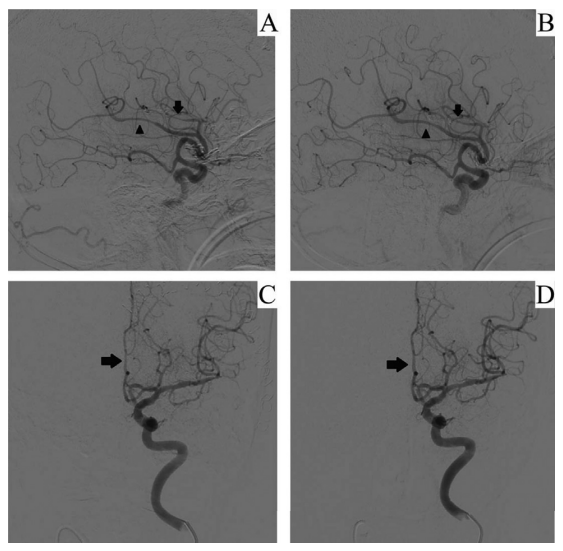

图2:病例1(A)动脉灌注尼莫地平前:胼周动脉(箭头)和胼缘动脉(箭头)血管痉挛。(B)动脉灌注尼莫地平后:双侧血管痉挛明显改善。病例2。(C)动脉灌注尼莫地平前;左侧大脑前动脉A2段(ACA)血管痉挛。(D) 动脉灌注尼莫地平后;A2节段直径明显改善。